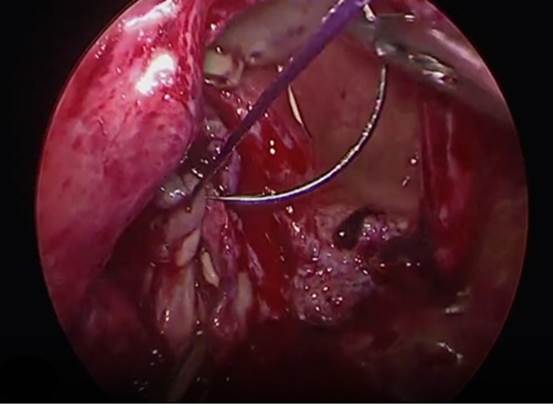

7. Cierre de la vagina y vejiga. El cual se realiza de forma separado en dirección horizontal de la vagina (Fig. 10) y vertical de la vejiga con monocryl 2-0 (Fig. 11).